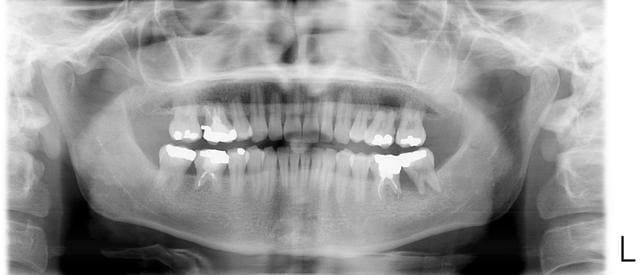

Jeune patient (29 ans)qui consulte pour des douleurs dans le secteur 36 37.

Inflamation gingivale tres importante, beaucoup de tartres pas de soins depuis 2003.

La 37 est mobile et je constate un abces parodontal.

ton patient présente des rhizalyses généralisées... et il a des problèmes paro+++. A T'il eu u traitement odf musclé? en tout cas ca sent l'implanto!

Si on regarde bien la pano, beaucoup de dents ont des racines résorbées. Les premières molaires sont celles qui semblent avoir le plus souffert. Peut-être à cause d'un traitement ortho.

La question qu'on peut se poser c'est si les rhizalyses sont actives ou pas. Si la cause est ortho et qu'aucun appareil n'est en place, est-il possible que les racines se résorbent encore davantage ?

ce cas me fait penser au sujet de ma thèse : le syndrome de Papillon Lefèvre.

signes associés, des desquamations au niveau des paumes des mains et des plantes de pieds.